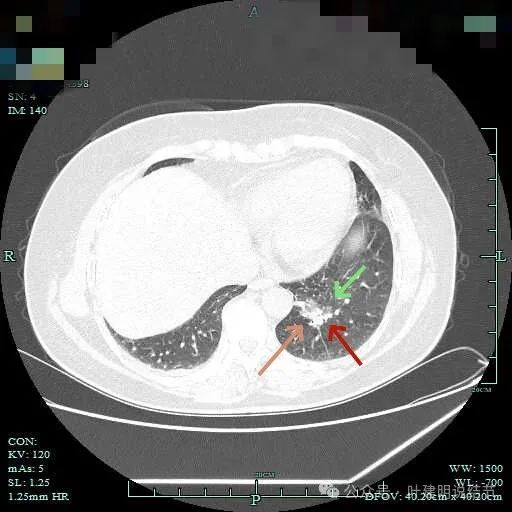

病灶轮廓欠清,较为散在,缺乏聚拢性,似乎有些像斑点状。

有少许磨玻璃成分出现,较前面层面整体轮廓显得清楚点。

到这层面,聚拢性较前明显,密度显杂乱。

磨玻璃成分更明显,实性成分也明显,实性部分收缩力不强,表面不平整,感觉边缘毛糙。